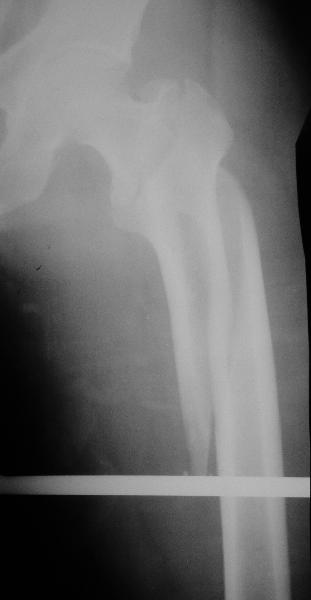

Как раз недавно у меня был примерный случай: больному 36 лет, поступил ночью, травма в результате мотоциклетной аварии, кроме чрезвертельного и спирального перелома левого бедра имеется переломы костей предплечья с этой же стороны. Скелетное вытяжение, а на следующий день больной про оперирован на ортопедическом столе с дистракцией. Чтобы не расколоть чрезвертельный перелом провели временную спицу ближе к переднему кортексу, из малого разреза костодержатель для репозиции, а фиксацию провели антиградным штифтом. Этапы операции на снимках.